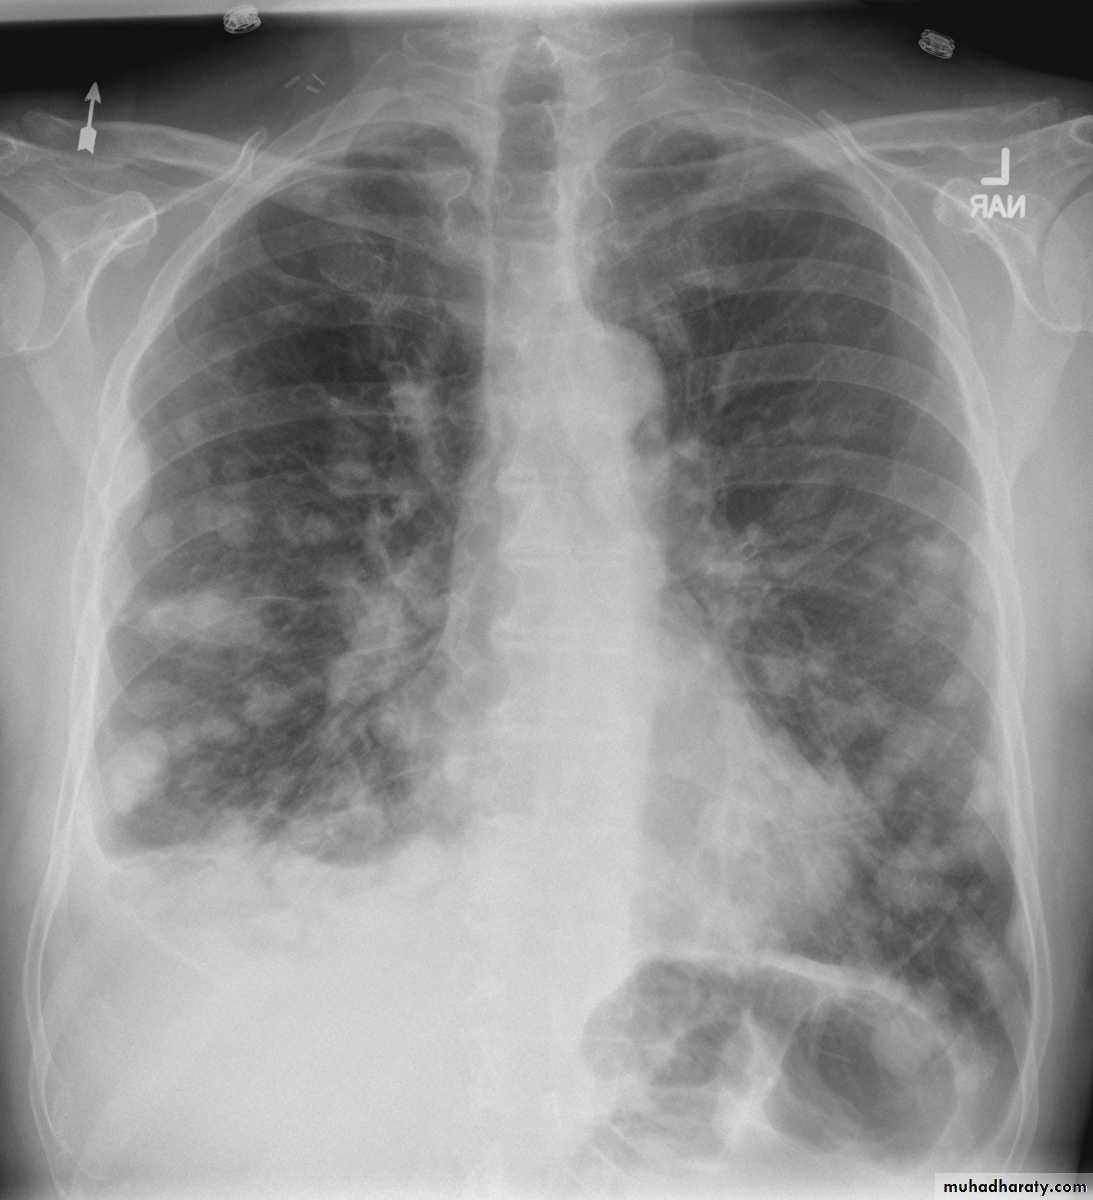

Chest radiography shows multiple pulmonary nodules of varying sizes consistent with metastatic cancer.

Multiple and bilateral secondaries